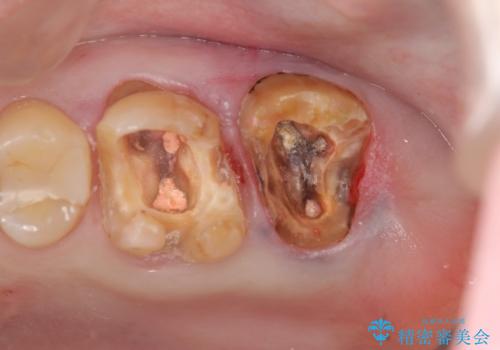

- 半年前から奥歯から嫌な臭いがする、と治療を求めて来院されました。

銀歯を除去したところ、虫歯が大きく再発しこのままではかぶせ直しができないような状況でした。

・根尖性歯周炎 →精密根管治療